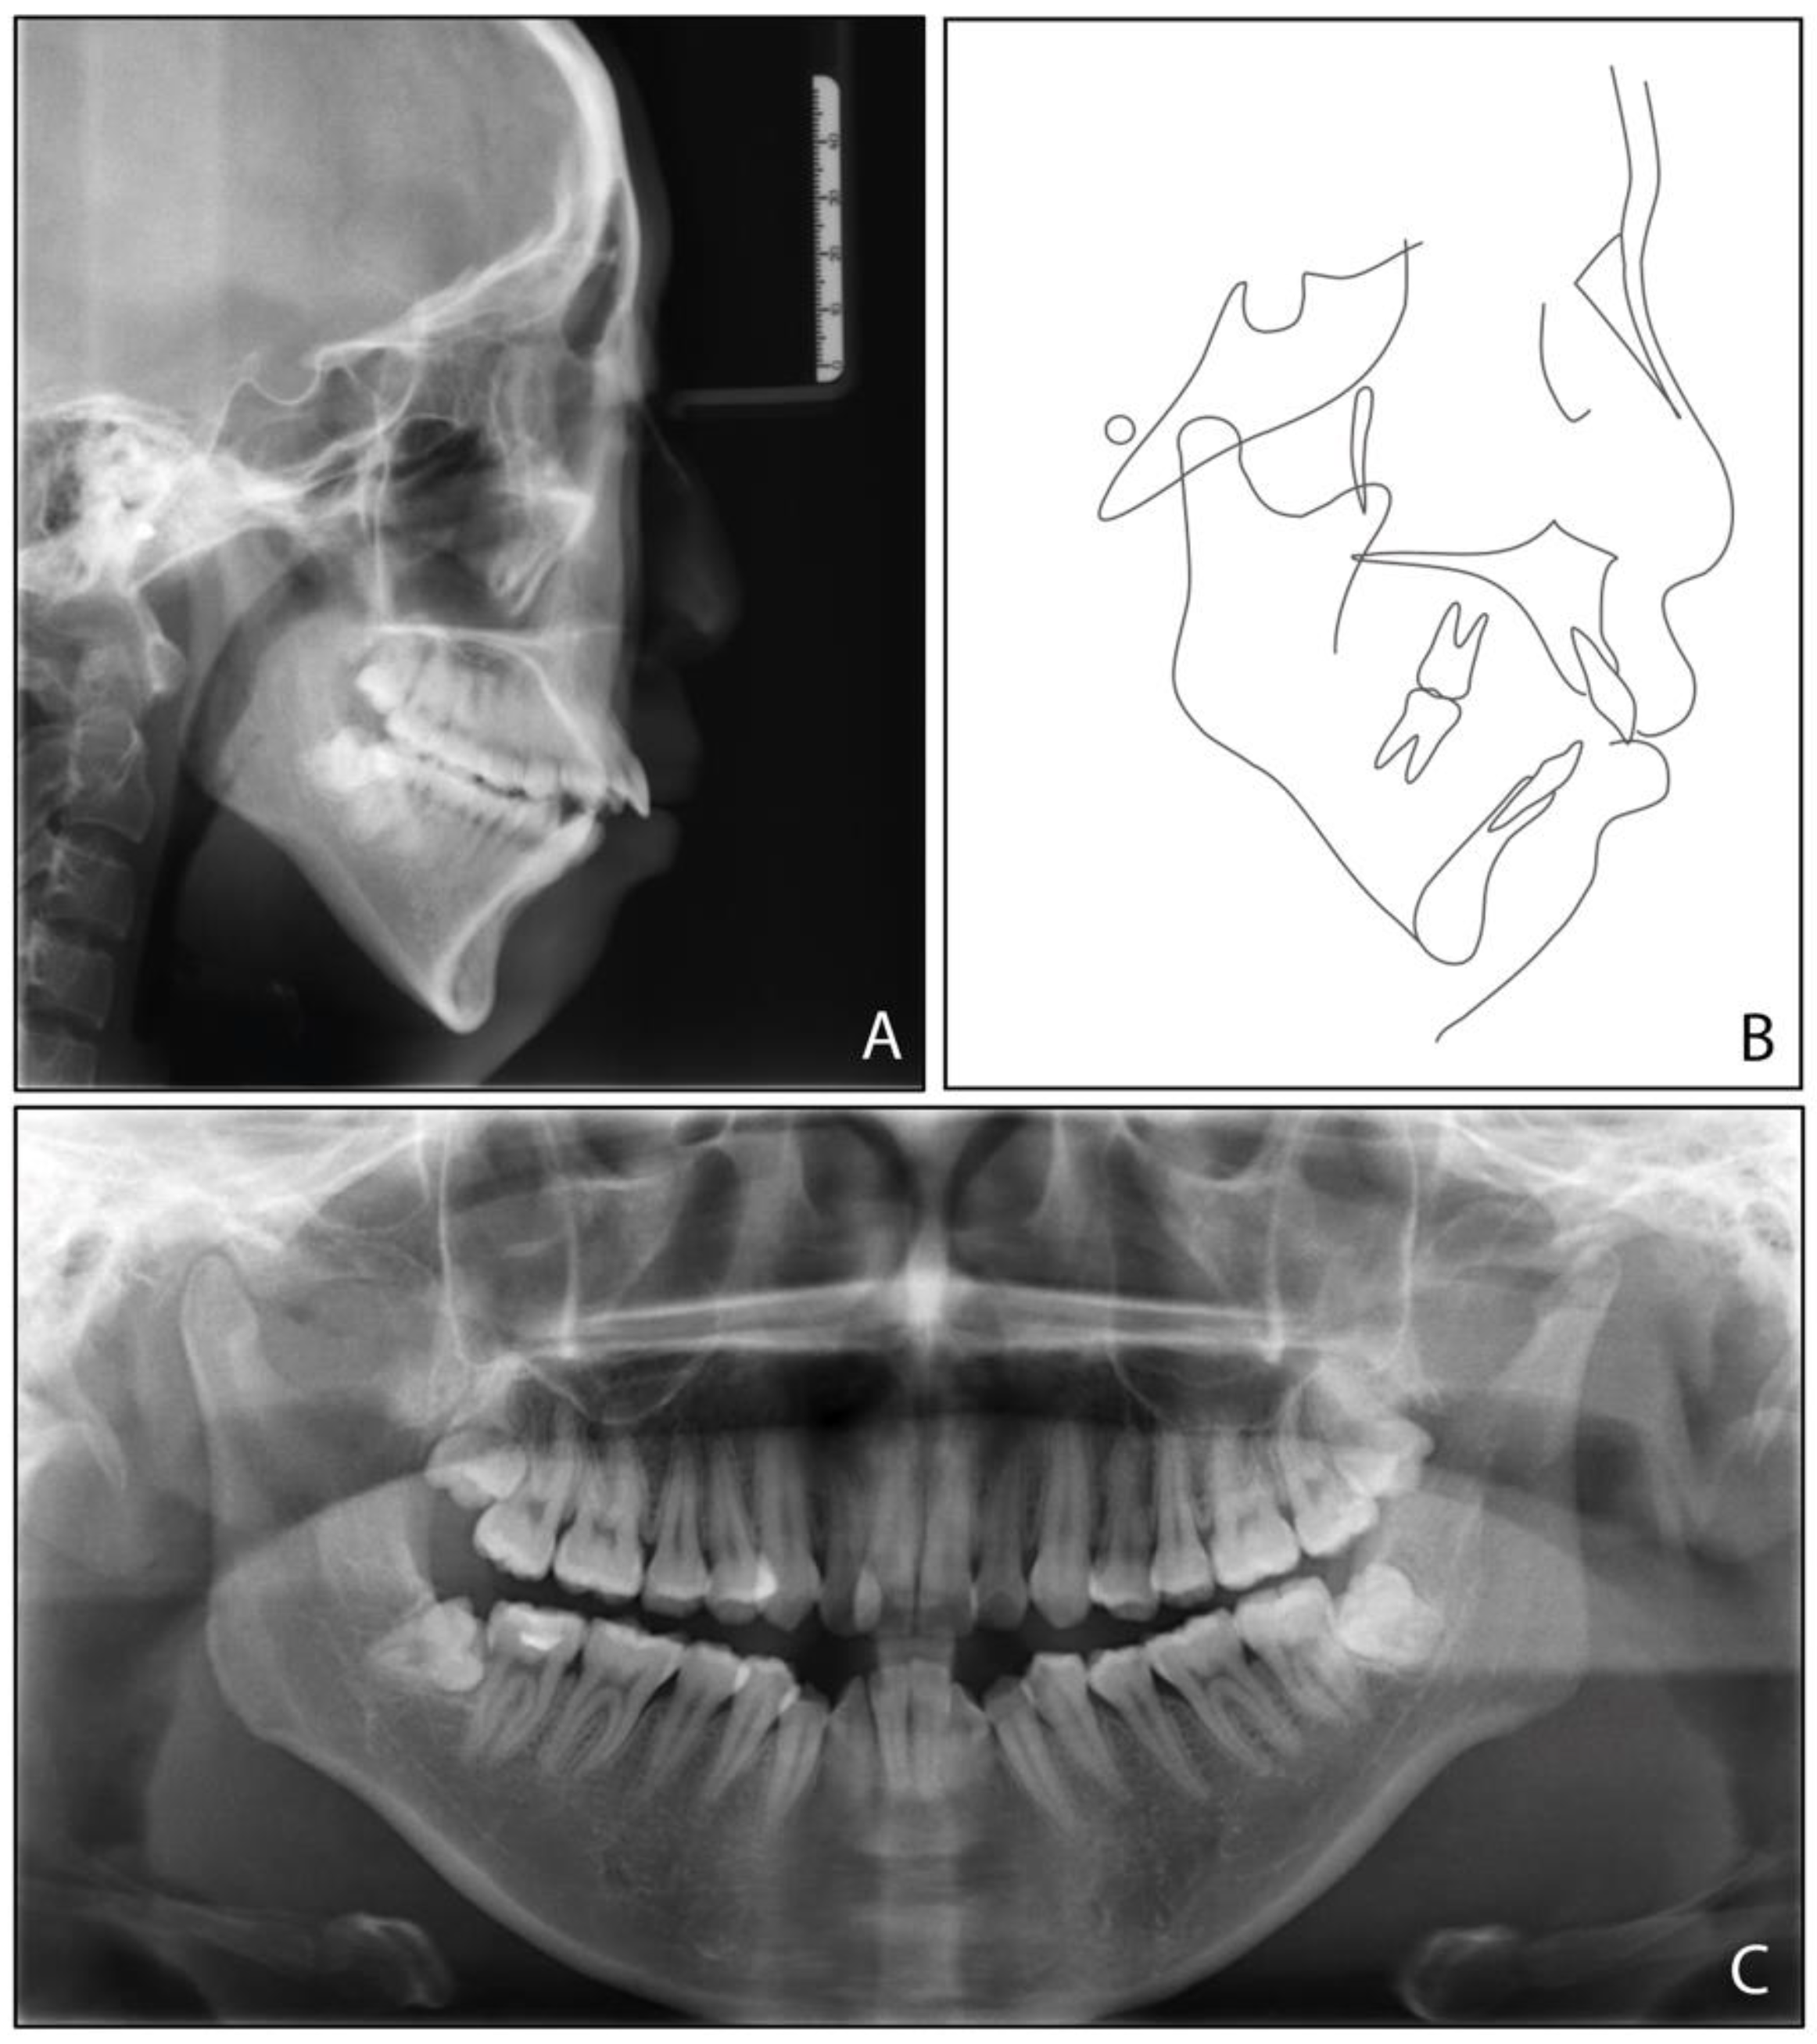

2.5. Treatment Results

| SNA (°) | 83.1 ± 2.7 | 80.3 | 79.7 | −0.6 |

| SNB (°) | 80.3 ± 2.6 | 71.9 | 73.9 | 2 |

| ANB (°) | 2.7 ± 1.8 | 8.4 | 5.8 | −2.6 |

| UI-SN (°) | 103.4 ± 5.5 | 106.9 | 91.9 | −15 |

| LI-MP (°) | 96.3 ± 5.4 | 97.2 | 90.8 | −6.4 |

| UI-LI (°) | 129.1 ± 7.1 | 102.7 | 129.1 | 26.4 |

| MP-SN (°) | 32.6 ± 6.9 | 55.8 | 52.9 | −2.9 |

| MP-FH (°) | 25.5 ± 4.8 | 45.6 | 42.8 | −2.8 |

| Wits (mm) | −1 ± 1 | 5.8 | 2.8 | −3 |

| A-OP (°) | 10 ± 3.58 | 12.2 | 14.5 | 2.3 |

| P-OP (°) | 14.9 ± 3.85 | 25.1 | 16.2 | −8.9 |

| U1-PP (mm) | 28 ± 1.6 | 32.9 | 26.6 | −6.3 |

| U6-PP (mm) | 23 ± 1 | 24.4 | 19.3 | −5.1 |

| L1-MP (mm) | 40.8 ± 1.8 | 44.1 | 39.3 | −4.8 |

| L6-MP (mm) | 31.1 ± 1.9 | 33.4 | 28.9 | −4.5 |

| Palatal-OP (°) | 10 ± 4 | 17 | 15.7 | −1.3 |

| Upper Face Height (mm) | 50 ± 2.5 | 56.4 | 55.8 | −0.6 |

| Lower Face Height (mm) | 65 ± 4.5 | 81.1 | 75.4 | −5.7 |

| Anterior Face Height (mm) | 115 ± 5.5 | 135.9 | 130.8 | −5.1 |

| Posterior Face Height (mm) | 45 ± 5 | 75.9 | 73.2 | −2.7 |

| P-A Face Height (%) | 65 ± 4 | 55.8 | 56 | 0.2 |

| Y-Axis (°) | 67 ± 5.5 | 84.7° | 83.1 | −1.6 |

| UL-E (mm) | −1.6 ± 1.5 | 5 | −1 | −6 |

| LL-E (mm) | −0.2 ± 1.9 | 7 | −1.3 | −8.3 |